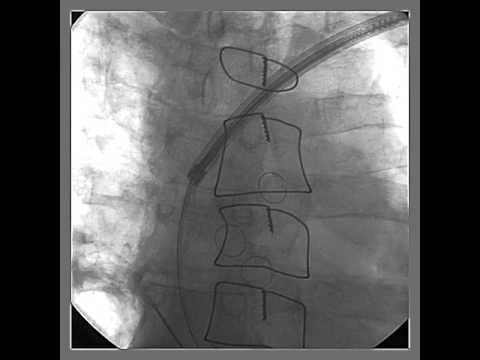

Video 56.3

Videos 56.3-56.5 Percutaneous pericardiocentesis was performed in a thin, elderly female who developed pericardial effusion and cardiac tamponade after impla...

Video 56.4

Videos 56.3–56.5 Percutaneous pericardiocentesis was

performed in a thin, elderly female who developed pericardial effusion and cardiac tamponade after implantation of a dual-chamber pacemaker. Pericardial access was obtained from subxiphoid approach. A guidewire was inserted up to the level of pericardial reflection underfluroscopy (clip 1), injection of dye into the pericardium confirmed pericardial effusion (clip 2), and after removal of blood from the pericardial space, the pericardial drain was left in situ (clip 3).